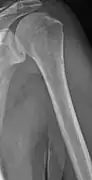

The diagnostic examination of a person with suspected multiple myeloma typically includes a skeletal survey. This is a series of X-rays of the skull, axial skeleton, and proximal long bones. Myeloma activity sometimes appears as "lytic lesions" (with local disappearance of normal bone due to resorption). And on the skull X-ray as "punched-out lesions" (pepper-pot skull). Lesions may also be sclerotic, which is seen as radiodense.[48] Overall, the radiodensity of myeloma is between −30 and 120 Hounsfield units (HU).[49] Magnetic resonance imaging is more sensitive than simple X-rays in the detection of lytic lesions, and may supersede a skeletal survey, especially when vertebral disease is suspected. Occasionally, a CT scan is performed to measure the size of soft-tissue plasmacytomas. Bone scans are typically not of any additional value in the workup of people with myeloma (no new bone formation; lytic lesions not well visualized on bone scan).

Multiple myeloma in the upper arm -

Humerus with multiple myeloma lesions -

Same humerus before, with just subtle lesions